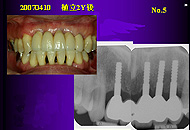

2.複数本植立と単独植立 1)複数本がすべて直径3mmの症例 : 21症例 67本

2)複数本の中に直径4または5mmを含む症例:14症例 24本

また複数本植立が原則で、「すべて直径3mm」は植立部位の骨幅が全域にわたって 狭い場合で、「直径4または5mmを含む」は幾分骨幅が広い部位に直径3mmより太いものを同時に植立できる場合である。 「直径3mm単独」は極力避けたい症例であることに間違いない。